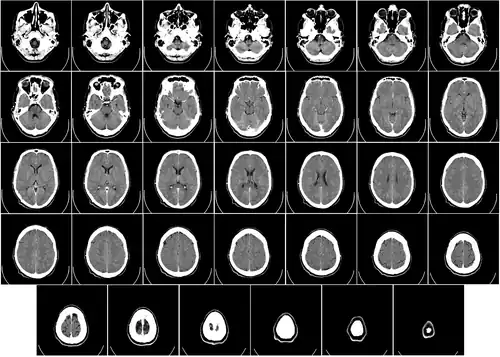

- ↑ Del Proyecto "Humano Visible" (Visible Human Project de la Biblioteca Nacional de Medicina de Estados Unidos. En este proyecto, dos cadáveres humanos (de un hombre y una mujer) fueron congelados y luego cortados en láminas delgadas, que fueron fotografiadas y digitalizadas individualmente. Esta sección está tomada a una pequeña distancia de la parte superior del cerebro, y muestra la corteza cerebral (la capa celular plegada al exterior) y la sustancia blanca subyacente, que consiste en tramos de fibra mielinizada que viaja hacia y desde la corteza cerebral.